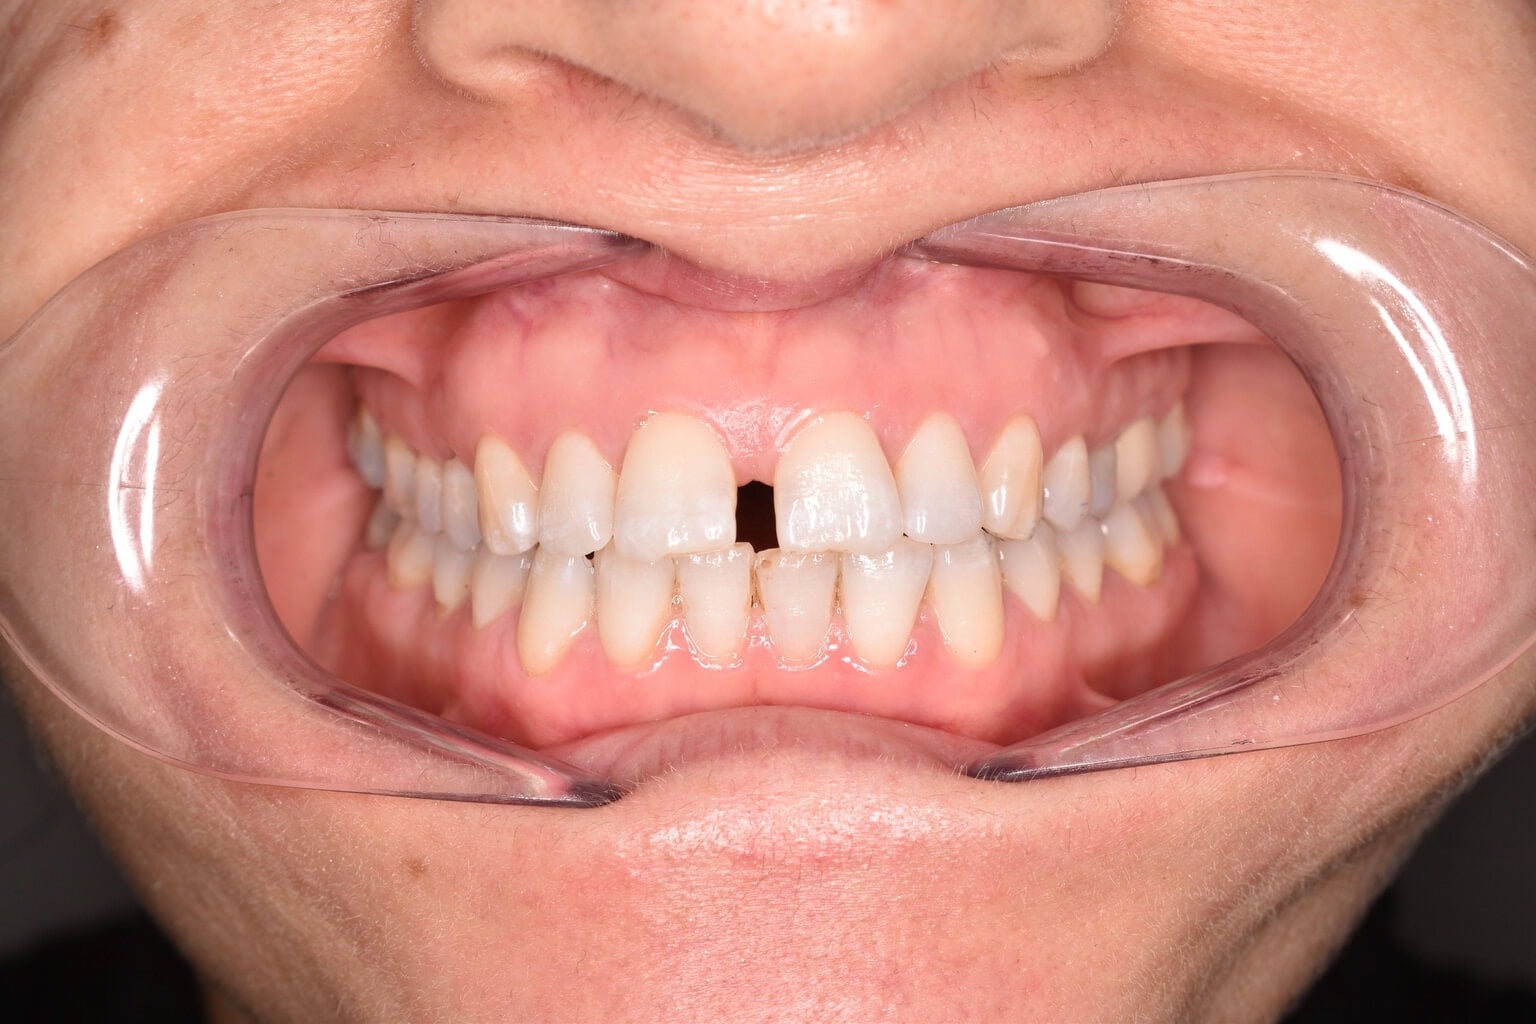

Vorher-Nachher-Ergebnisse

Echte Ergebnisse. Echte Menschen.

Jede Behandlung bei TIEFBLAU Kieferorthopädie ist so individuell wie der Mensch dahinter. In unserer Vorher-Nachher-Galerie zeigen wir Ihnen echte Behandlungsergebnisse aus unserer Praxis in der Kölner Südstadt: Schonend erzielt, präzise geplant und mit dem Anspruch, den wir seit über 40 Jahren an jede Behandlung stellen.

Die Bilder geben Ihnen einen Eindruck davon, was moderne Kieferorthopädie leisten kann, ob bei Kindern, Jugendlichen oder Erwachsenen.

Der sichtbare Unterschied

Dokumentiert. Überzeugend. Nachhaltig.